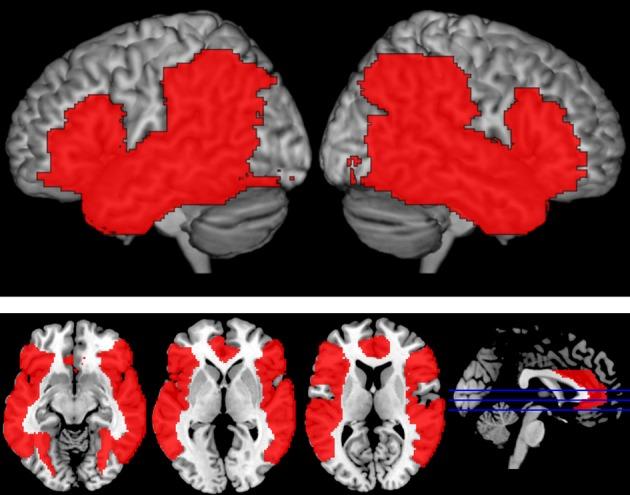

Language production requires multiple stages of processing (e.g., semantic retrieval, lexical selection), each of which may involve distinct brain regions. Distractor words can be combined with picture naming to examine factors that influence language production. Phonologically-related distractors have been found to speed picture naming (facilitation), while slower response times and decreased accuracy (interference) generally occur when a distractor is categorically related to the target image. However, other types of semantically-related distractors have been reported to produce a facilitative effect (e.g., associative, part-whole). The different pattern of results for different types of semantically-related distractors raises the question about how the nature of the semantic relation influences the effect of the distractor. To explore the nature of these semantic effects further, we used functional MRI to examine the influence of four types of written distractors on brain activation during overt picture naming. Distractors began with the same sound, were categorically-related, part of the object to be named, or were unrelated to the picture. Phonologically-related trials elicited greater activation than both semantic conditions (categorically-related and part-whole) in left insula and bilateral parietal cortex, regions that have been attributed to phonological aspects of production and encoding, respectively. Semantic conditions elicited greater activation than phonological trials in left posterior MTG, a region that has been linked to concept retrieval and semantic integration. Overall, the two semantic conditions did not differ substantially in their functional activation which suggests a similarity in the semantic demands and lexical competition across these two conditions.

语言产生需要多个处理阶段(例如,语义检索、词汇选择),每个阶段都可能涉及不同的大脑区域。干扰词可以与图片命名相结合,以研究影响语言产生的因素。研究发现,与语音相关的干扰词会加快图片命名的速度(促进),而当干扰词与目标图像在类别上相关时,通常会导致反应时间变慢和准确性降低(干扰)。然而,其他类型的语义相关干扰词已被报道会产生促进作用(例如,联想、部分-整体)。不同类型的语义相关干扰词产生不同结果的模式提出了一个问题,即语义关系的性质如何影响干扰词的效果。为了进一步探讨这些语义效应的性质,我们使用功能磁共振成像(fMRI)研究了四种类型的书面干扰词对显性图片命名过程中大脑激活的影响。干扰词的开头音相同,与目标图像类别相关,是要命名的物体的一部分,或者与图片无关。与语音相关的试验在左侧脑岛和双侧顶叶皮层中引起的激活大于两种语义条件(类别相关和部分-整体),这两个区域分别被归因于产生和编码的语音方面。在左后颞中回(MTG)中,语义条件引起的激活大于语音条件,这一区域与概念检索和语义整合有关。总的来说,这两种语义条件在功能激活方面没有显著差异,这表明这两种条件在语义需求和词汇竞争方面具有相似性。